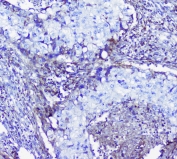

IHC staining of FFPE human pancreatic cancer with LUM antibody at 1ug/ml. HIER: boil tissue sections in pH6, 10mM citrate buffer, for 10-20 min followed by cooling at RT for 20 min.